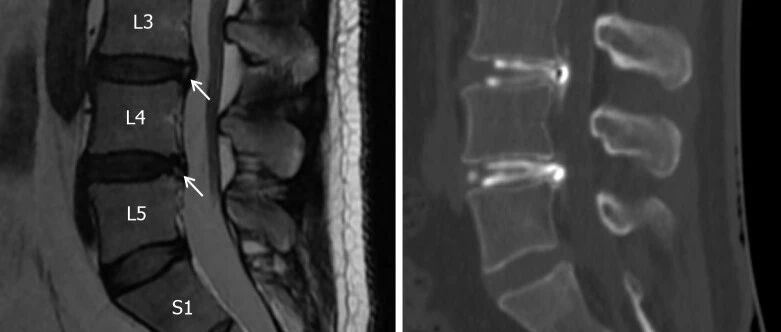

腰椎峡部解剖与峡部裂